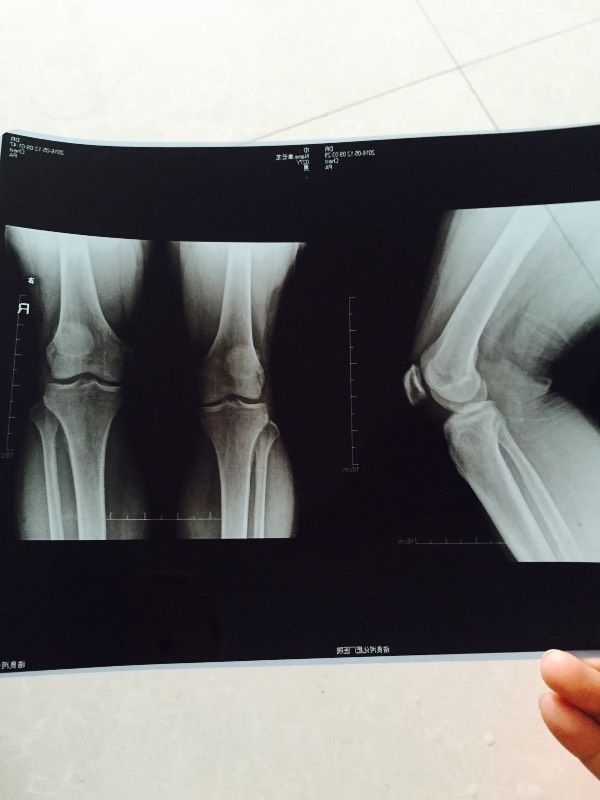

我弟弟腿部关节疼痛,在医院拍片了,医生也没说啥问题.请大家帮我看

图片尺寸 600x800